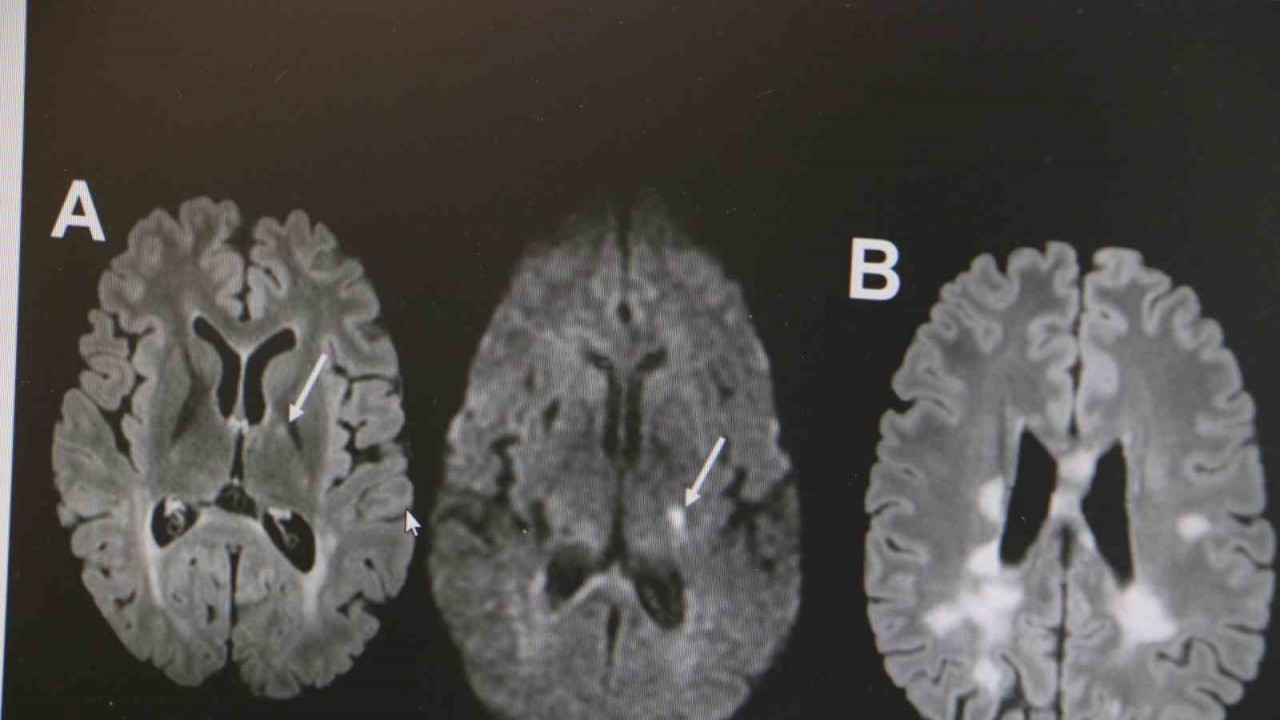

MS hastalığının otoimmün bir hastalık olduğunu belirten Dr. Demir, "Vücuttaki bağışıklık sisteminin beyindeki sinir hücrelerinin yalıtımını sağlayan sinir kılıfına, beyin hücrelerine saldırması sonucu beyinde hasar oluşmaktadır. Hastalığın isminden de anlaşılacağı üzere MS hastalığı birçok bölgede skar dokusuna sebep olabilmektedir. Özellikle hastalarda kol ve bacaklarda güçsüzlük, uyuşmalar, görme kayıpları, baş dönmesi, çift görmeler gibi birçok nörolojik belirti oluşabilmekte. Uluslararası MS federasyonuna göre dünyada 3 milyona yakın MS hastası bulunmakta. Her 5 dakikada bir MS hastalığı tanısı koyulmaktadır. Ülkemizde de yaklaşık 60 bin MS hastası bulunmakta. MS hastalığı ekvatordan uzaklara gidilen ülkelerde, özellikle Avrupa ülkeleri, Amerika ve Kanada gibi ülkelerde sıklığı gittikçe artmakta" dedi.

MS hastalığının kadın popülasyonunda daha sık görüldüğünün altını çizen Demir, "Kadınlarda erkeklere göre bu hastalık yaklaşık 2 kat daha sık görülmekte. MS hastalığı özellikle ataklarla seyreden bir hastalıktır. Hastaların yüzde 85’inde relapsing remitting form dediğimiz atak formuyla seyretmektedir. MS hastalığının tanısı klinik olarak kesin tanı konulabilse de günümüz şartlarında MR çekilmeden kesin tanı konulmaması önerilmektedir. MS hastalığının tedavisine gelecek olursak, kesin bir tedavisi yoktur. Ancak son 10 yılda çok sayıda ilaç kullanıma girmiştir. Bu açıdan MS hastalığı kontrol edilebilir bir hastalıktır. MS hastalığına bağlı ataklara karşı hastalara steroid tedavisi vermekteyiz. MS hastalarında görülen her şikayet atak olmayabilir. Özellikle idrar yolu enfeksiyonu, üst solunum yolu enfeksiyonu, aşırı egzersiz durumlarında, sıcak bir ortamda bulunma gibi durumda hastalarda ısı artışına bağlı olarak daha önceden var olan semptomlarda kötüleşme olabilir. Bunlar daha çok yalancı atak diyebiliriz. Ancak atak diyebilmemiz için şikayetin en az 24 saat sürmesi gerekmektedir" ifadelerinde bulundu.